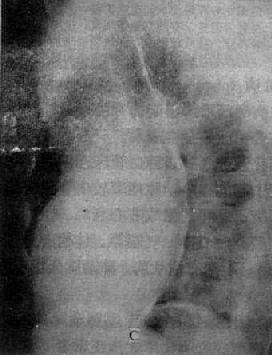

图3-2-21 房间隔缺损

右前斜位:右心室增大,肺动脉段突出,心前间隙变窄,无左心房增大后前位:心增大,呈二尖瓣型,右心房及右心室增大,肺动脉段突出,肺纹理增强左前斜位:右心房及右心室增大,左心室被增大的右心室推向后